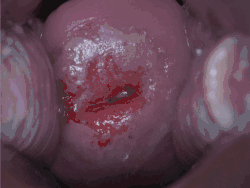

Positive visual inspection with acetic acid of the cervix for CIN-1

Cervical intraepithelial neoplasia (CIN), also known as cervical dysplasia, is the abnormal growth of cells on the surface of the cervix that could potentially lead to cervical cancer.[1] More specifically, CIN refers to the potentially precancerous transformation of cells of the cervix.

CIN most commonly occurs at the squamocolumnar junction of the cervix, a transitional area between the squamous epithelium of the vagina and the columnar epithelium of the endocervix.[2] It can also occur in vaginal walls and vulvar epithelium. CIN is graded on a 1–3 scale, with 3 being the most abnormal (see classification section below).